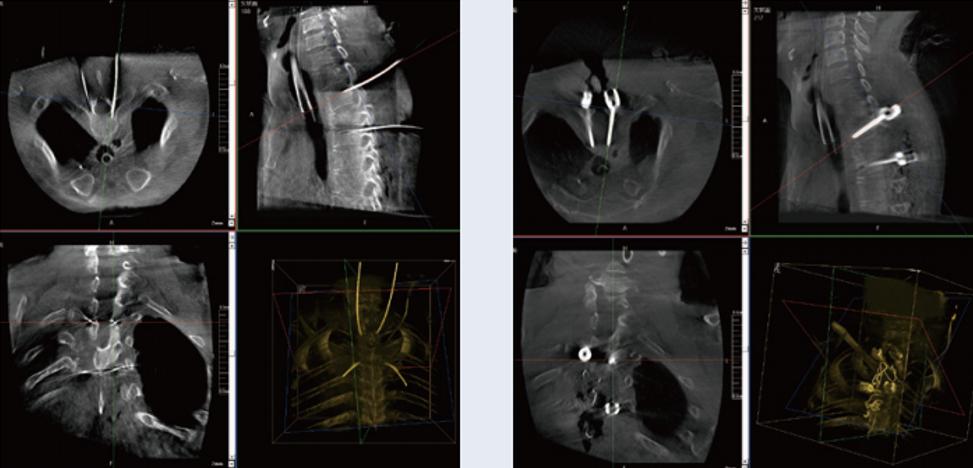

螺釘規(guī)劃后的圖像

植入螺釘后的圖像

術(shù)中三維C形臂與脊柱導(dǎo)航機(jī)器人配合應(yīng)用,實(shí)現(xiàn)準(zhǔn)確定位,確保了手術(shù)安全、高效完成。術(shù)后二維、三維影像顯示手術(shù)效果良好,達(dá)到預(yù)期目的。

普愛醫(yī)療三維C形臂提供了高質(zhì)量的術(shù)中實(shí)時三維圖像數(shù)據(jù),保障了脊柱導(dǎo)航機(jī)器人手術(shù)的準(zhǔn)確度和安全性,取得不錯的手術(shù)效果。同時,術(shù)中三維C形臂特有的斷層成像,能幫助醫(yī)生在術(shù)中非常直觀地判斷螺釘植入的準(zhǔn)確度。